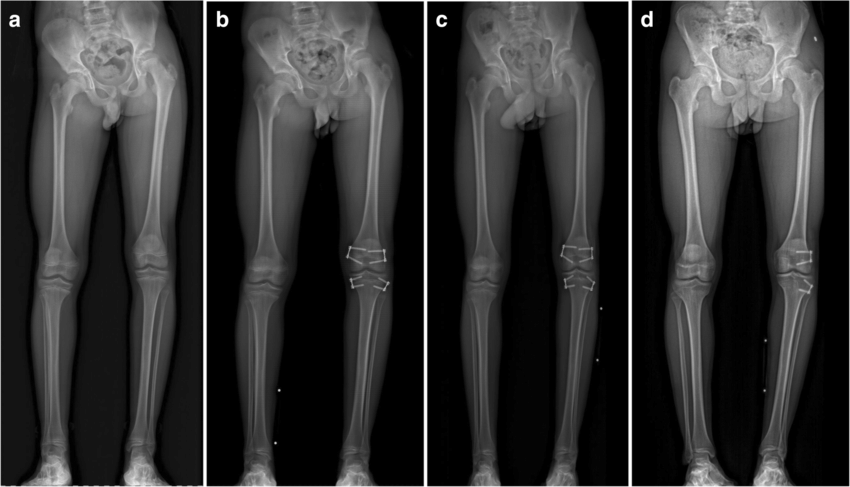

• *Epiphysiodesis*: A procedure to slow down the growth of the longer limb, allowing the shorter limb to catch up. Typically performed in children nearing the end of their growth period.

• *Limb Lengthening*: Involves cutting the bone and gradually lengthening it using an external fixator or internal lengthening device. This is a lengthy process but can effectively correct significant discrepancies.